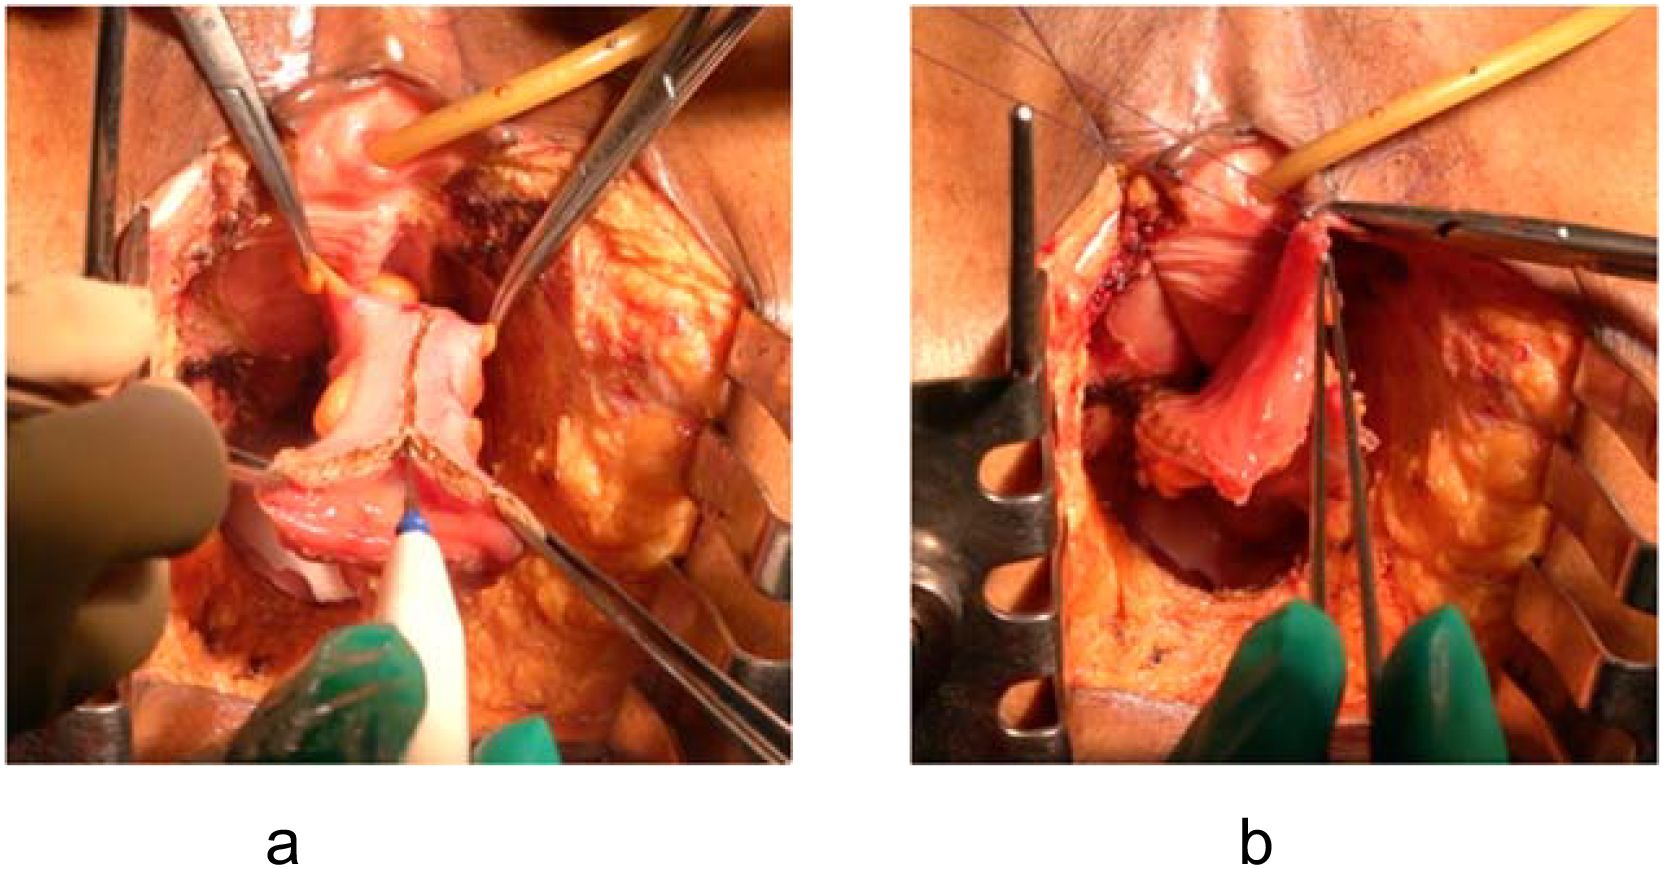

CT scan showing two images: (a) a coronal view of the pelvis, highlighting a radiodense mass with an arrow; (b) a sagittal view of the abdomen and pelvis, indicating the same mass with another arrow.

Figure 5. Postoperative CT imaging of mucosa-removed colonic flap. (a) Coronal view; (b) Sagittal view. Arrows indicate optimal alignment of the flap forming a neoperitoneal diaphragm, effectively preventing perineal herniation.